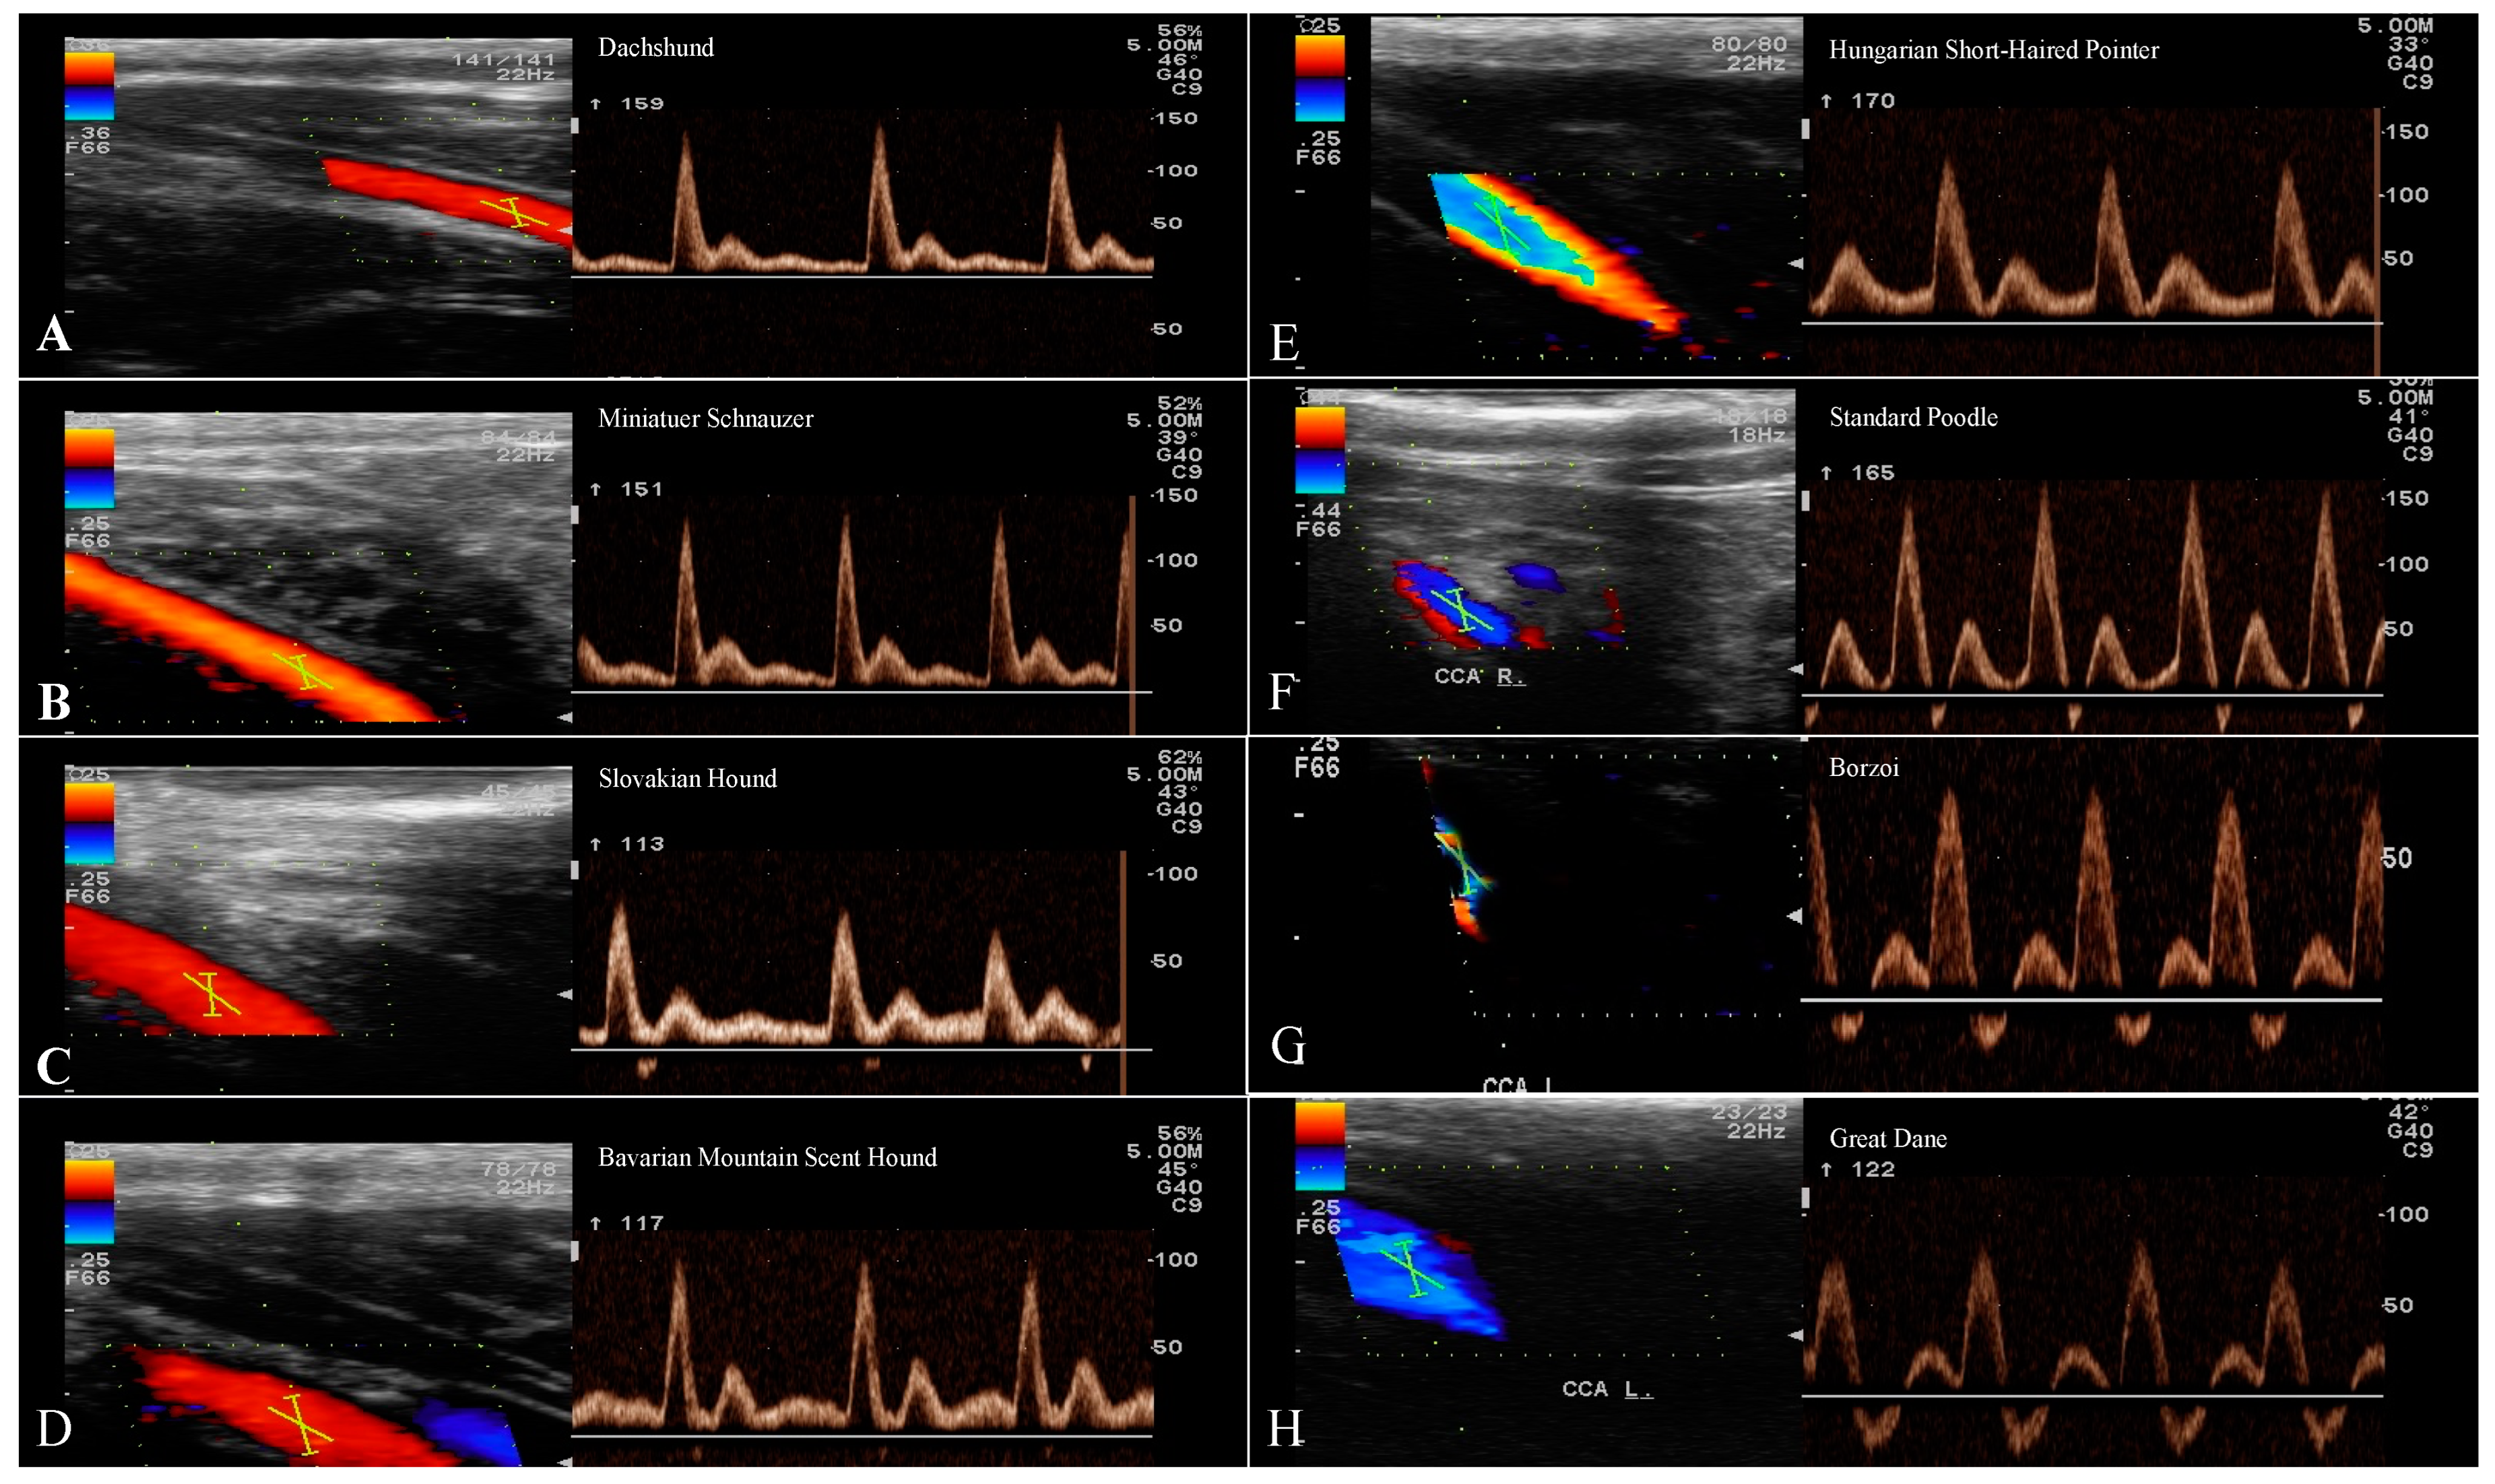

| Small breeds | Dachshund | 13 | 2.5 | 0.84 | 130.6 ± 15.56 | 17.98 ± 4.48 | 7.84 ± 2.1 |

| Miniature Schnauzer | 13 | 2.3 | 0.84 | 127.3 ± 13.49 | 19.57 ± 3.68 | 6.85 ± 1.7 | |

| Medium breeds | Slovakian Hound | 13 | 3.5 | 0.81 | 108.1 ± 17.39 | 19.96 ± 6.83 | 6.47 ± 2.9 |

| Bavarian Mountain Scent Hound | 13 | 3.6 | 0.76 | 115.4 ± 21.7 | 30.71 ± 7.1 | 3.88 ± 0.4 | |

| Large breeds | Hungarian Short-Haired Pointer | 13 | 3.5 | 0.76 | 119.9 ± 16.07 | 27.52 ± 5.63 | 4.63 ± 0.98 |

| Standard Poodle | 13 | 3.5 | 0.79 | 106.7 ± 9.2 | 22.31 ± 4.49 | 5 ± 0.77 | |

| Giant breeds | Borzoi | 13 | 3.2 | 0.78 | 96.54 ± 6.21 | 22.3 ± 1.56 | 4.49 ± 0.54 |

| Great Dane | 13 | 5.7 | 0.66 | 94.37 ± 18.7 | 31.43 ± 12 | 3.40 ± 0.95 | |